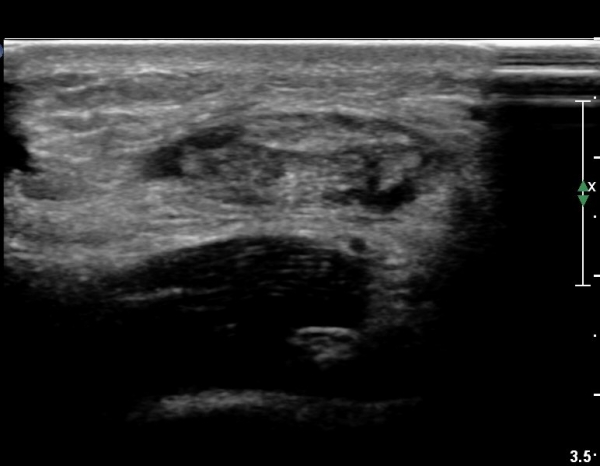

¾ÆÅ³·¹½º°Ç Ⱦ´Ü¸é°Ë»ç¿¡¼ ¾ÆÅ³·¹½º°Ç Àú¿¡ÄÚ ºÎÁ¾, ¿¬°á¼º ¼Ò½Ç, °ÇÁÖÀ§ ¼ö¾×Àú·ù ¼Ò°ßÀ» º¸ÀÓ(»çÁø 6, 7, 8).